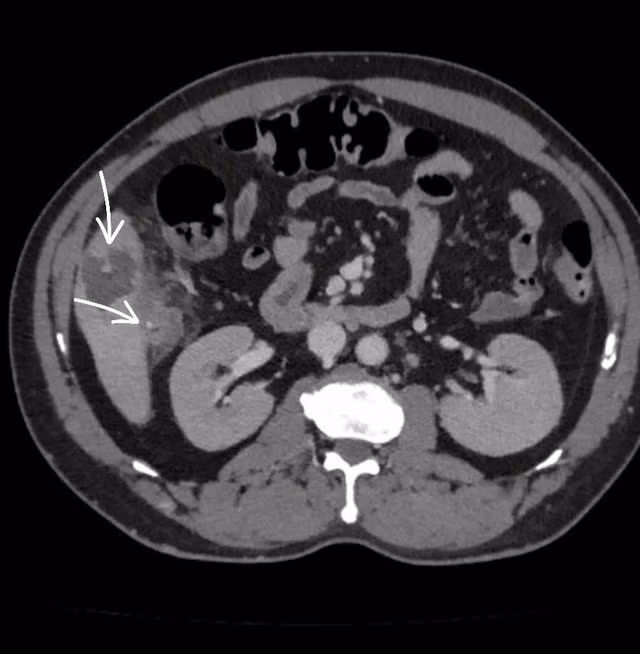

Kết quả chẩn đoán hình ảnh (CT scan) cho thấy một mảnh xương nhỏ xuyên qua thành đại tràng tại góc gan, găm vào nhu mô gan hạ phân thùy V, tạo ổ áp xe kích thước 56x36mm, kèm viêm dày thành đại tràng vùng góc gan. Đây là nguyên nhân chính gây ra ổ nhiễm trùng nguy hiểm. Bệnh nhân nhanh chóng được các bác sĩ phẫu thuật nội soi, lấy dị vật và xử lý ổ áp xe thành công. Sau phẫu thuật, bệnh nhân đáp ứng với điều trị, tình trạng dần ổn định và được chuyển sang Khoa Ngoại Tiêu hóa để tiếp tục điều trị.